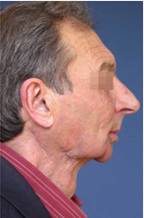

Пациент с тежка травматична деформация на дясната орбита, реконструирана с костни присадки от черепния свод – случай на доц. Джоров.

Корекция на брадата преди и след лечението – случай на доц. Джоров